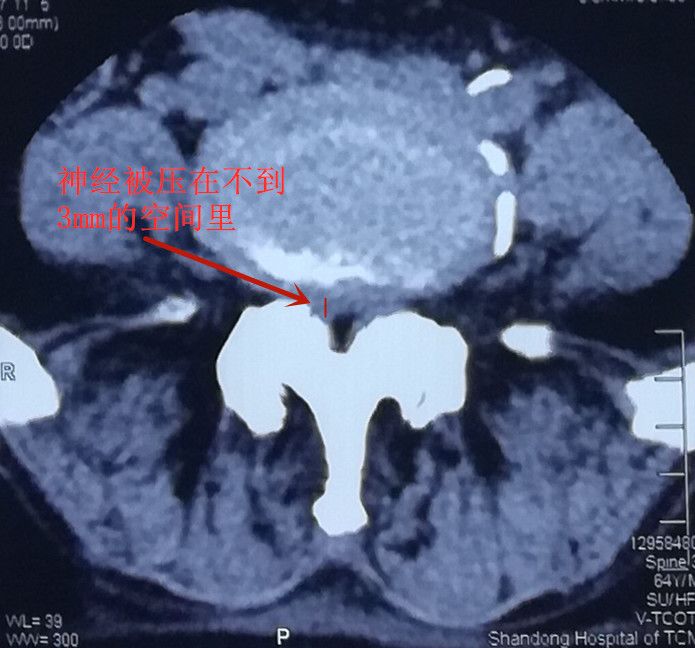

家住滨州市的马大爷,双下肢疼痛难忍,影响睡眠。老伴晚上帮他揉腿才能略有缓解,借助拐杖才能勉强行走。经过检查,马大爷的疼痛是由严重的椎管狭窄压迫神经所致。正常椎管的矢状径(既前后径)为十几毫米,他只剩下三四毫米了,加上长期卧床,马大爷右腿疼痛越来越重,到省城很多医院就诊,专家建议进行开放手术治疗,要打开椎板进行神经减压。 但马大爷患有前列腺肿瘤,他和家属都不敢尝试做大手术,于是四处打听有没有微创的办法能解决疼痛,打听到淄博市桓台县人民医院疼痛科微创水平比较高,遂来我院咨询。疼痛科汤明主任介绍,目前我院脊柱内镜技术的飞速发展,脊柱内镜能够解决所有类型的腰椎管狭窄,而且内镜治疗,创口仅0.7厘米,不剥离肌肉,恢复快,不容易留后遗症。最终患者决定在我院做微创脊椎内镜手术,手术顺利,将增生的骨质、肥厚的黄韧带全部清理干净,手术后当天就睡了个好觉,隔了一天就可以下地活动了,疼痛也都消失了。